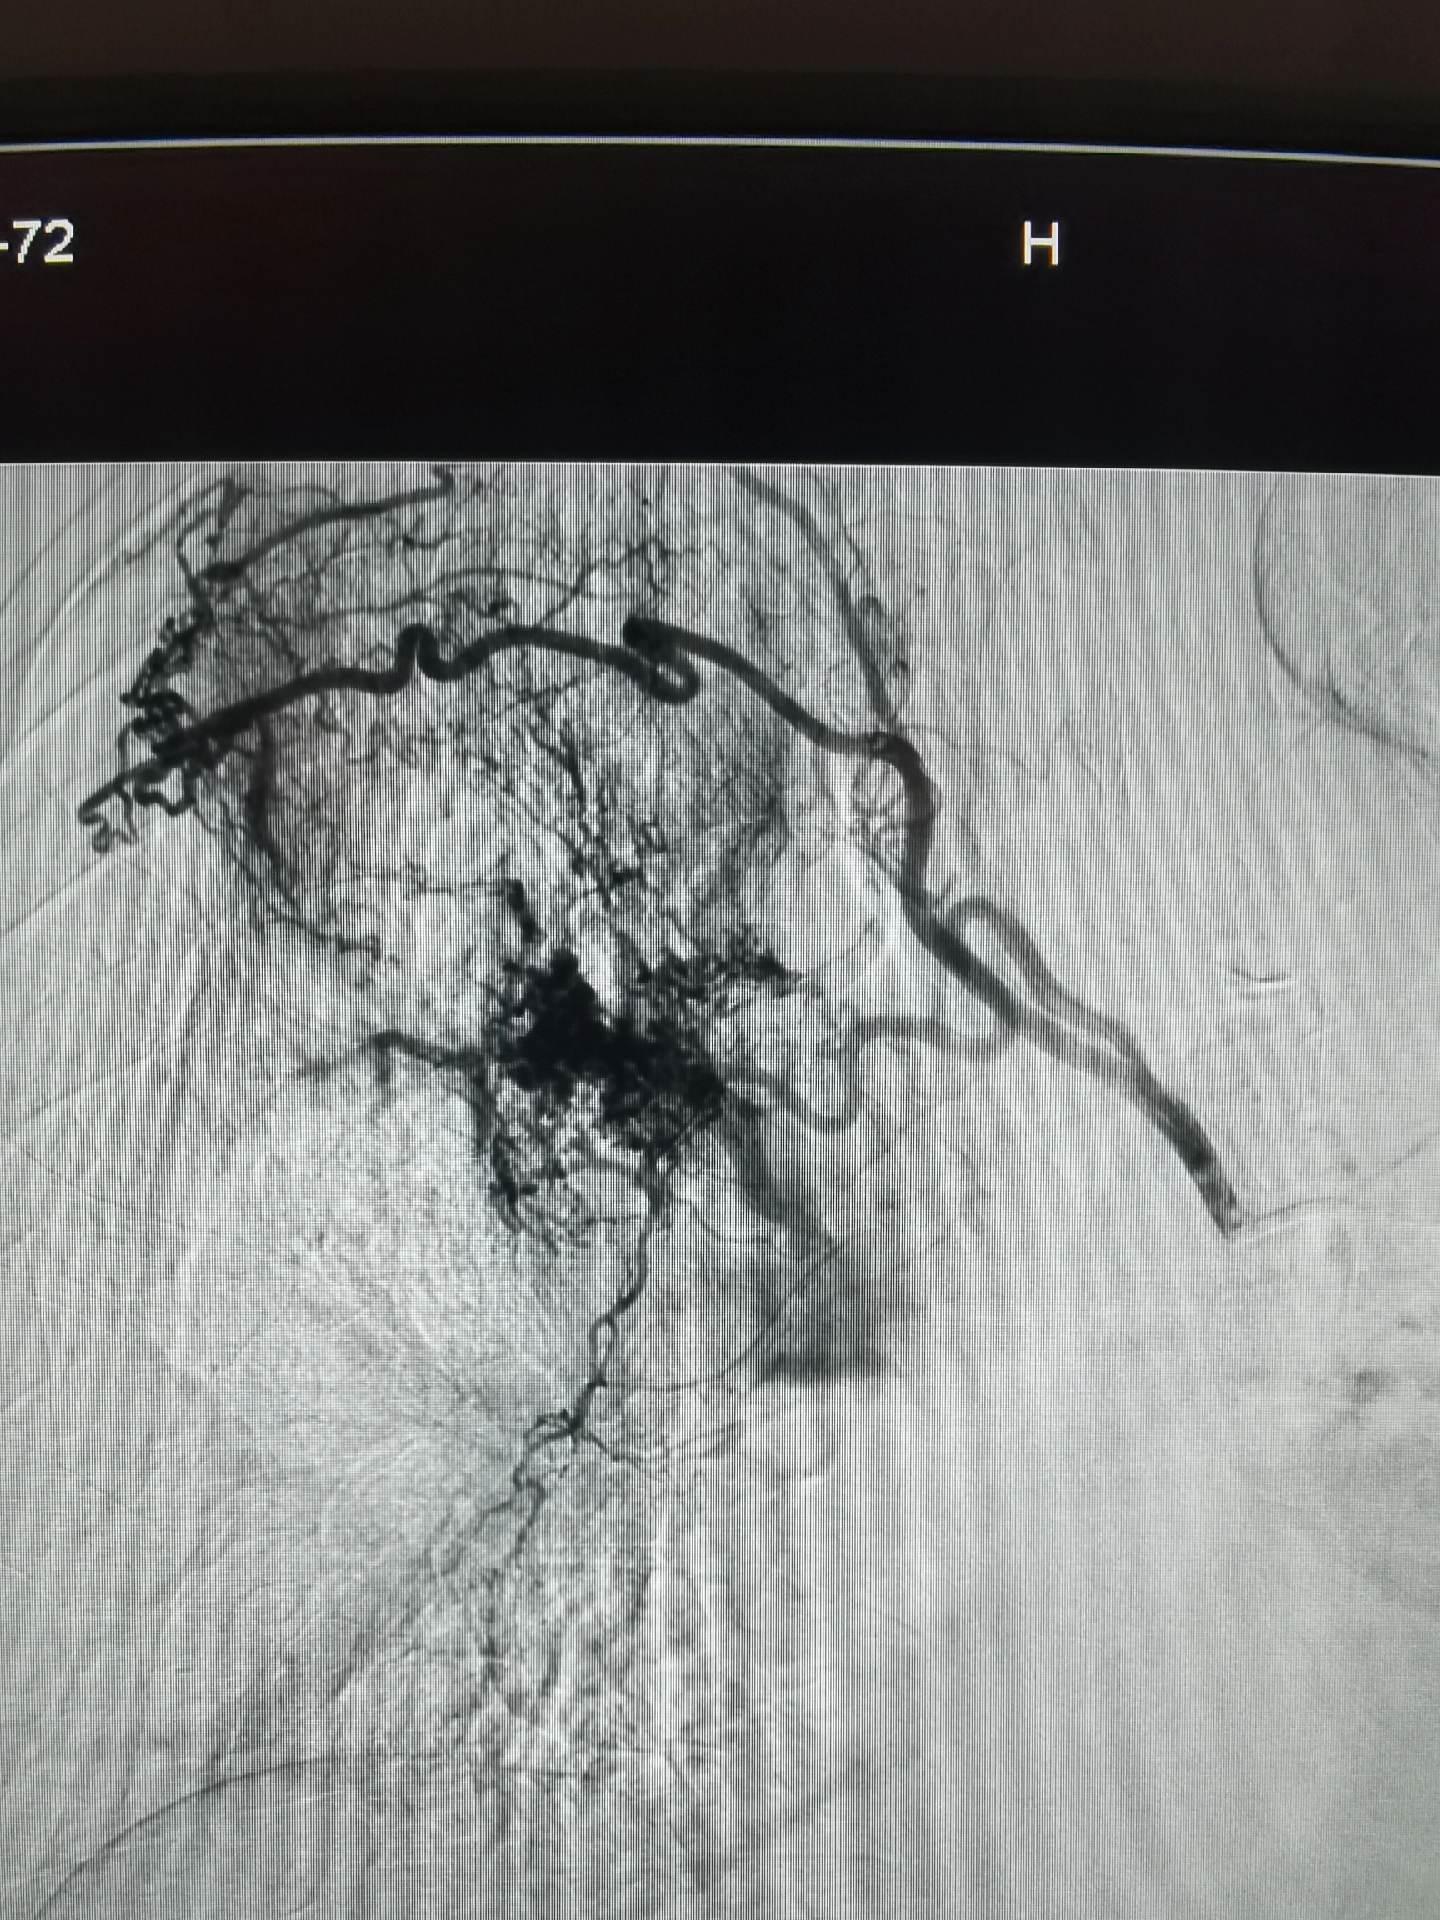

急诊咯血介入治疗,胸上动脉,锁骨下动脉分支,右侧支肋共干支气管动脉,右侧支气管动脉,食管固有动脉,左侧支气管动脉,右侧膈动脉,术前CTA以及选择合适的大导管和微导管真的重要,不仅能超选到位,又能快速完成超选。